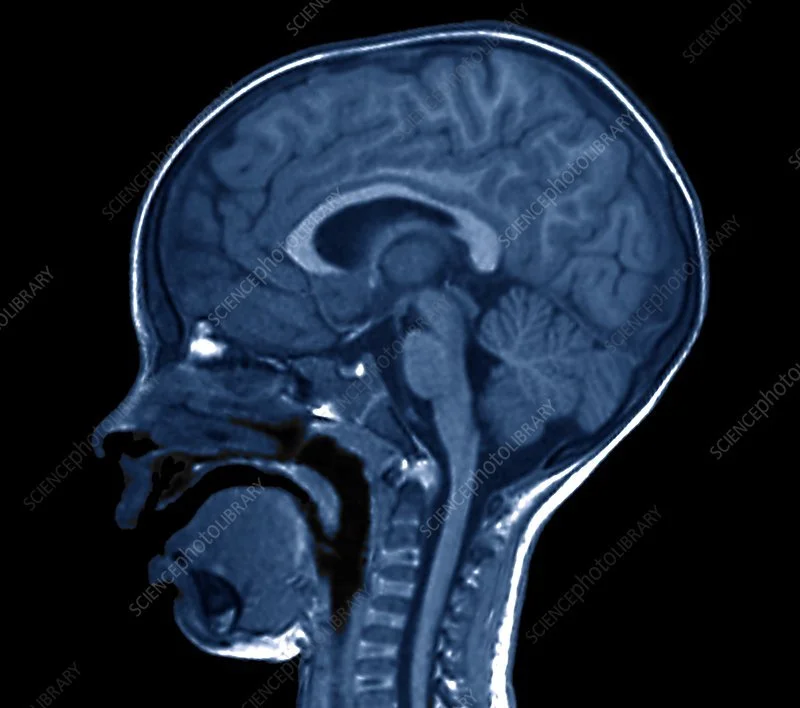

So now you know why those things are super important, the rest of this will make more sense. This first picture is a NORMAL brain. Source: Science Photo Library